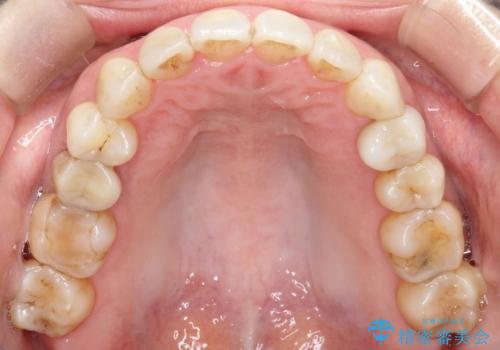

【インビザライン 】前歯を下げたい

- 前歯の凸凹と、前突を主訴に来院されました。

インビザライン にて治療を行なっております。

治療期間中はゴムかけを行なってもらうことで、前歯を下げることができました。